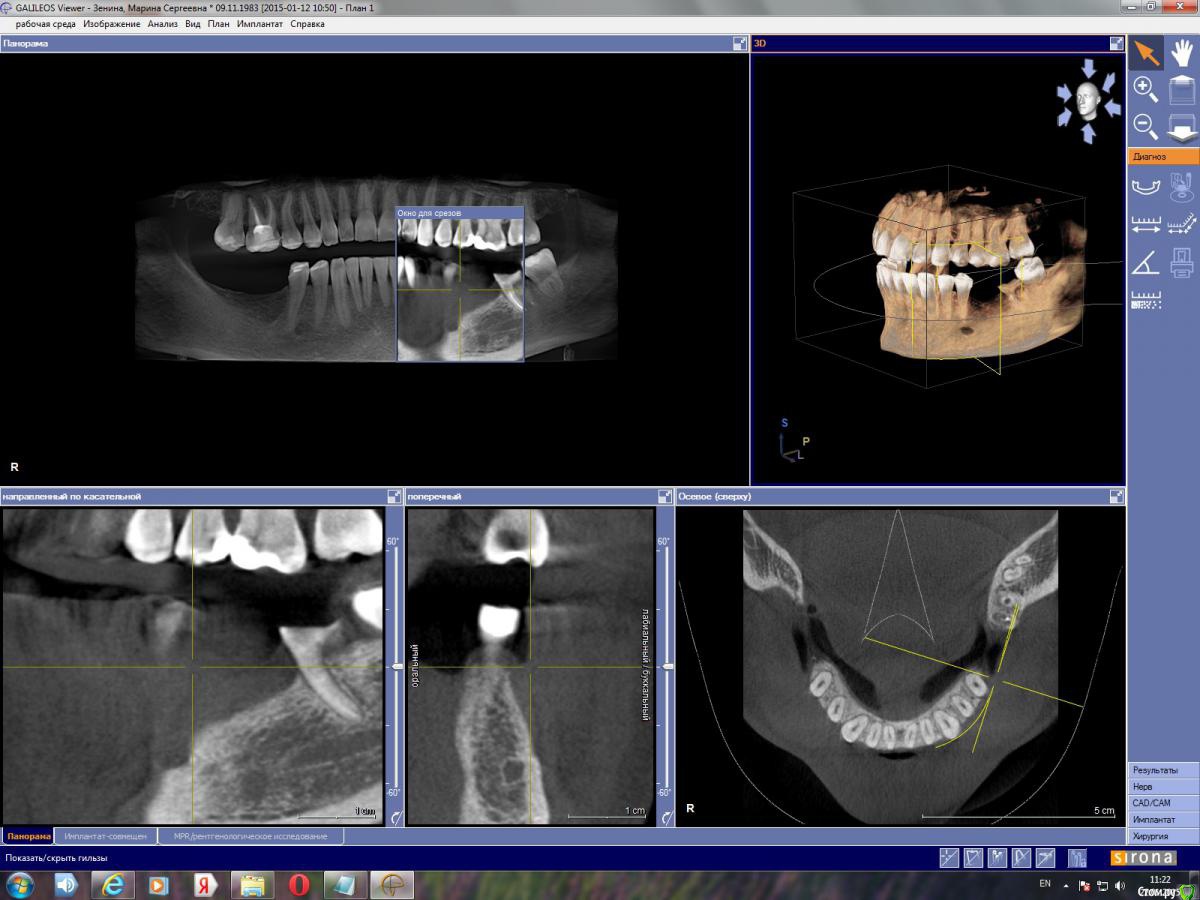

марин зенина Опубликовано 17 января, 2015 Автор Поделиться Опубликовано 17 января, 2015 https://yadi.sk/d/gpmuDkTXdwj3M архив моей КТ вместе с программой для просмотра GalileosViewer. Посмотрите, пжста, можно ли здесь обойтись без костной пластики. Ссылка на комментарий

марин зенина Опубликовано 21 января, 2015 Автор Поделиться Опубликовано 21 января, 2015 пожалуйста, подскажите нужно ли здесь наращивание кости) Ссылка на комментарий

Большой Зеленый Опубликовано 21 января, 2015 Поделиться Опубликовано 21 января, 2015 пожалуйста, подскажите нужно ли здесь наращивание кости)Нарежте скриншотов и выложите сюда.Никто не станет качать столько ненужной информации. Ссылка на комментарий

марин зенина Опубликовано 22 января, 2015 Автор Поделиться Опубликовано 22 января, 2015 выкладываю скриншоты) Ссылка на комментарий

red_butler Опубликовано 22 января, 2015 Поделиться Опубликовано 22 января, 2015 поставьте перекрестие такhttp://i052.radikal.ru/1501/27/c9ad0f50b717.jpg Ссылка на комментарий

марин зенина Опубликовано 22 января, 2015 Автор Поделиться Опубликовано 22 января, 2015 так? Ссылка на комментарий